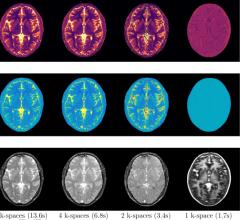

MRI creates images from the magnetic resonance created in hydrogen atoms when they are polarized and an electromagnetic pulse is used to knock them off axis. This section includes MR analysis software, MRI scanners, gadolinium contrast agents and related magnetic resonance imaging accessories.